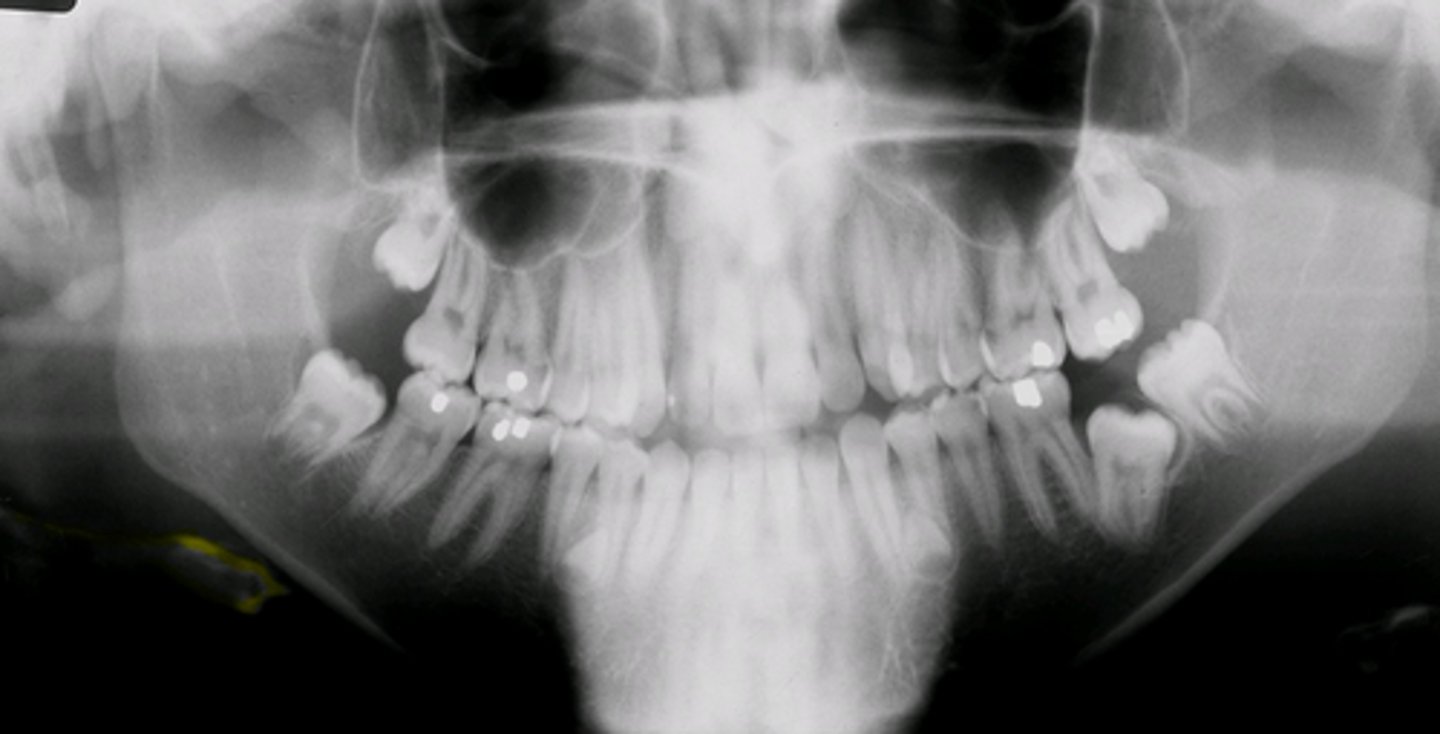

panoramic radiograph

provides full view of the upper & lower jaw

panoramic radiograph purpose

allows us view your head, neck, & jaw, & how they work together as a whole

Impacted third molars are best seen w/what type of radiograph?

Panoramic

supernumerary teeth are best detected using what type of image receptor?